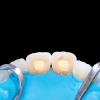

(2.) The pulp chambers of a patient’s maxillary central incisors being accessed for the placement of sodium perborate for the walking bleach technique.

Figure 2

Internal bleaching using sodium perborate mixed with water, which is known as the "walking bleach" technique, offers a safer treatment modality with a substantially decreased risk of internal resorption (Figure 1). One downside to this approach is that it requires several follow-up appointments to replace the internal bleach before the treatment is completed (Figure 2). In addition, the temporary materials placed over the access oftentimes fall out. With the walking bleach technique, a balance must be struck in which the temporary barrier is thick enough to prevent easy dislodgment but not so thick that it prevents an adequate amount of bleaching material from being placed. Using a more permanent material over the access is one way to circumvent this issue; however, the access will likely get larger each time it is removed, which is also less than ideal.